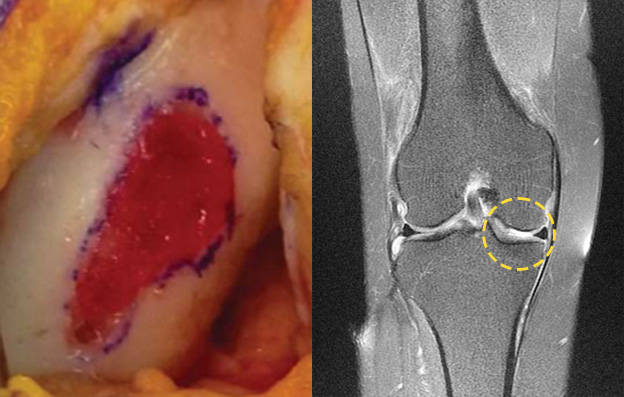

그렇지 않습니다. 퇴행성 관절염 처럼, 연령이 많은 환자에서

퇴행성 관절염의 범위가 넓은 경우 줄기세포 치료로 완전한

효과를 거둘 수가 없습니다. 비교적 젊은 연령에서 국소적

손상이 있는 경우는 효과가 인정되고 있습니다.

특히, 0자형 다리 변형이 있는 경우 또한 줄기세포 치료의

적절한 대상이 아닙니다. 즉, 줄기세포 치료는 만능이 아니다

라는 점을 인지하셔야 합니다.

- 환자 동의하에 게시된이미지

입니다.